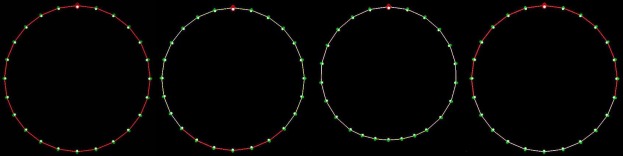

2D Ring (24–200 nodes)

Demonstrated macro-reentrant circuits and reentry tachycardia. Tests boundary conditions and circular wave propagation.